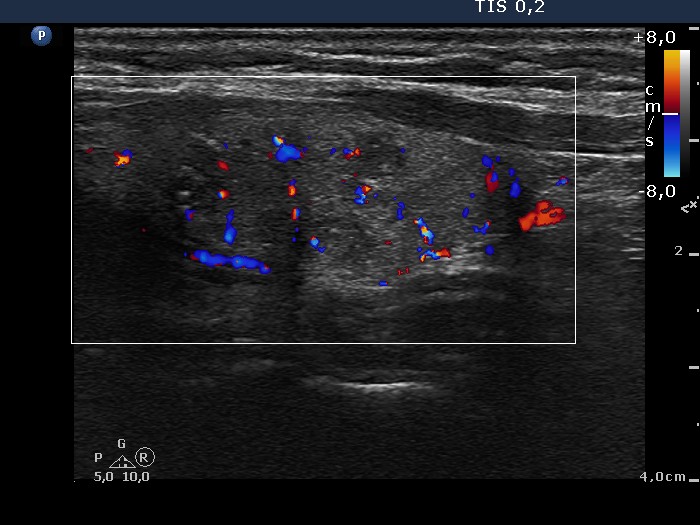

Right lobe, longitudinal scan

Left lobe, longitudinal scan, color Doppler mode. The intranodular vascularization is a bit increased.